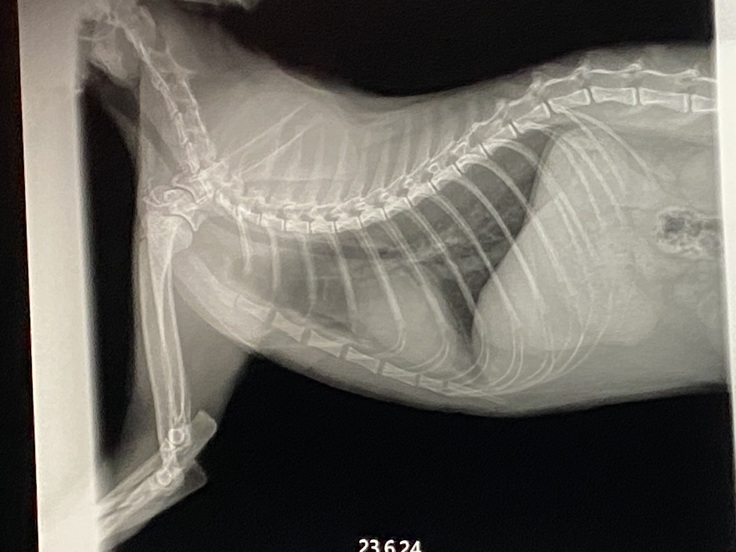

①画像は、6/14の朝呼吸が荒く、病院に行った時のものです。

獣医師から、胸水が溜まり、また、腫瘍により、気管が下から押され、とても苦しかったらだろうと説明がありました。

②画像は、胸水を抜いた後です。

全ての胸水は抜いていませんが、120cc抜いたとのことでした。心臓の下に3センチの腫瘍が見つかりました。

③画像は、6/24ものです。

6/17にやった抗がん剤が効き、腫瘍が見えなくなったと獣医師から説明がありました。ただ、猫白血病は予後が悪いらしく、この先、うまくいくとは限らないとの説明を受けました。